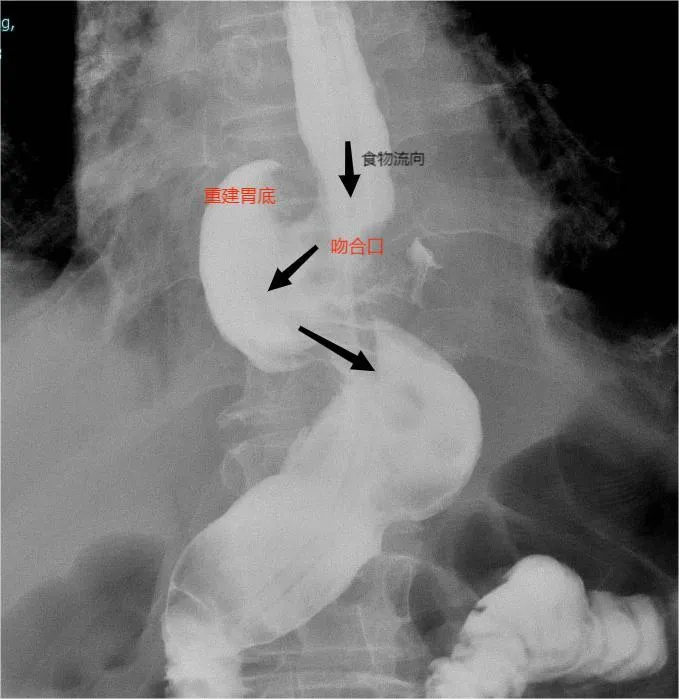

關(guān)鍵手術(shù)步驟(如下圖):

3.符合人體生理解剖的消化道重建方式,術(shù)后不易發(fā)生反流性食管炎、吻合口狹窄等并發(fā)癥。